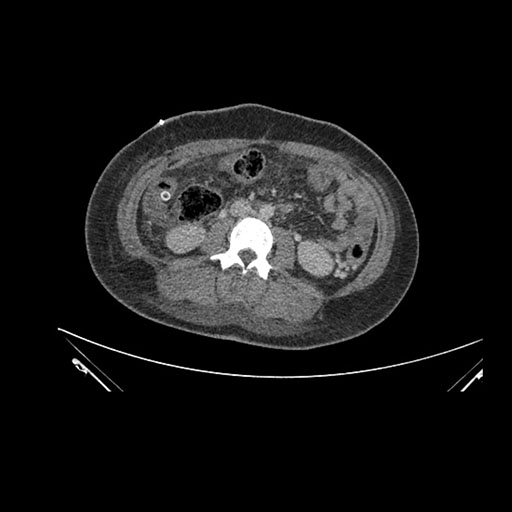

Imaging Analysis

Look through the patient's CT scan to identify any areas of concern for the necessary procedure.

Based on initial findings, which issue(s) would you be most concerned about?